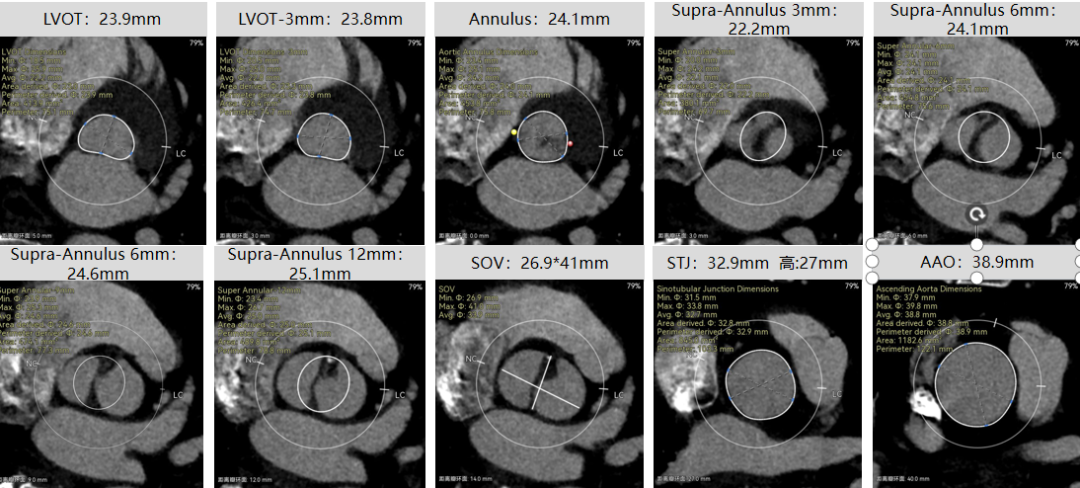

袁祖贻院长 西安交通大学第一附属医院 创新见证中国领跑,数据积累筑牢临床效果 韩克教授 西安交通大学第一附属医院 干瓣技术革新赋能特殊人群治疗,“量体裁衣”筑牢安全防线 患者病史 主诉与现病史:5年前因"血友病,血尿”就诊于当地医院,住院期间行心动超声提示主动脉瓣及二叶瓣畸形,无胸闷气短,无胸痛,咳嗽咳痰,无头晕,恶心呕吐等不适。未予以干预,后规律复查心超,3周前复查心超提示:主动脉瓣二瓣化畸形并重度狭窄,升主动脉内径明显增宽。 既往史:确诊血友病A型40年 术前超声提示:先天性主动脉瓣二叶式畸形,主动脉瓣中度狭窄,升主动脉增宽,左室舒张功能减低,EF73% 术前CT:Type0型二叶瓣,瓣叶增厚无钙化,主动脉瓣环径24.1mm,LVOT23.9mm;双侧冠脉开口高度可,窦部空间可,STJ、升主动脉内径可;预估冠脉低风险;主动脉水平夹角37.1°,主动脉弓角、弓距可;左室内径可;外周入路无明显迂曲,无钙化;双侧股动脉内径可,右侧股动脉低分叉。 手术策略 推荐右侧股动脉为主入路,左侧股动脉为辅入路。右股分叉上方1mm穿刺;仅舒张期时相,需根据球扩结果评估瓣膜尺寸,推荐使用18mm球囊进行预扩;预装AV26瓣膜。 手术过程 在右股动脉穿刺建立通路后,顺利送入大鞘。18mm球囊预扩后评估无腰无漏,后将Prostyle A® AV26瓣膜精准释放于目标位置,术后即刻造影显示无明显反流,无瓣周漏,平均跨瓣压差由术前的100mmHg降至2mmHg,患者血流动力学显著改善,术后超声证实瓣膜启闭良好。 主动脉根部造影 18球囊预扩 定位 稳定释放后脱钩 最终造影形态位置良好 外周血管造影,无血管并发症 术后超声显示无生物瓣位置固定瓣膜功能正常,无瓣周漏。 Prostyle A®预装干瓣——助力临床最优化解决方案 流入端桶状设计:流入端桶状的设计,锚定迅速,有效减少释放步骤,提升植入稳定性; 平衡的收腰设计:二叶瓣患者对瓣膜径向支撑力提出更高要求,Prostyle A®均衡的收腰设计可更好适应二叶瓣解剖,保证了EOA,有效降低了循环崩溃风险,提高瓣膜的耐久性; 预装干瓣 便捷顺安:金仕生物专利抗钙化技术运用纳米技术去除组织内的细胞碎片和磷脂,封闭游离醛基,从根本上阻断了瓣膜钙化的多项因素,显著提升了瓣膜的耐久性;同时,相比较传统戊二醛保存方式,干式存储最大限度的保留心包的亲水亲油平衡,还原组织天然曲柔性,进一步保障了瓣叶开合,保证长期耐久性。 专家简介 袁祖贻 西安交通大学第一附属医院(点击查看专家详细简历) 韩克 西安交通大学第一附属医院(点击查看专家详细简历) · END ·